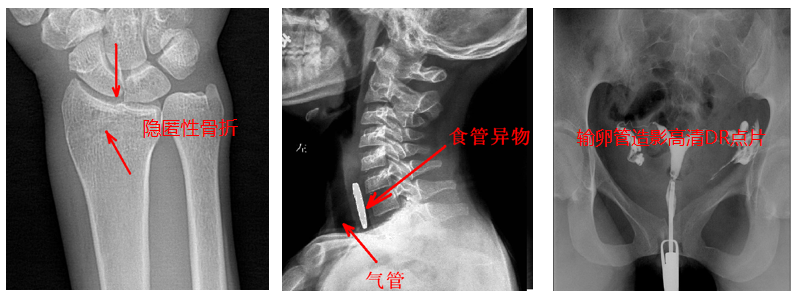

2.?dāng)?shù)字透視。適用于全身各部位透視(如胸透、腹透等),以及在透視下DR點(diǎn)片等;動(dòng)態(tài)采集速度≥25幀/秒,應(yīng)用于消化科、泌尿科、婦科等。

4.?dāng)?shù)字造影。PLD5500B動(dòng)態(tài)DR機(jī)適用于各種普通及特殊造影,如口服膽囊造影、靜脈膽道造影、T管造影、逆行胰膽管造影(ERCP)、靜脈腎盂造影(IVP)、子宮輸卵管造影、脊髓造影等,主要應(yīng)用于消化內(nèi)外科、泌尿外科、婦科、神經(jīng)內(nèi)外科等。

5.準(zhǔn)確點(diǎn)片。在透視下準(zhǔn)確找到病灶部位,這對(duì)于早發(fā)現(xiàn)隱匿性骨折有著不可替代的作用。更難能可貴的是,它可以在透視情況下進(jìn)行整骨復(fù)位以及術(shù)后在透視下檢查。